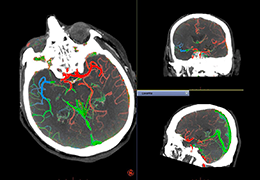

High-quality and fast 3D reconstruction and 3D rendering

Performs 3D reconstruction and volume rendering.

Multi-planar slicing.

Oblique slicing.